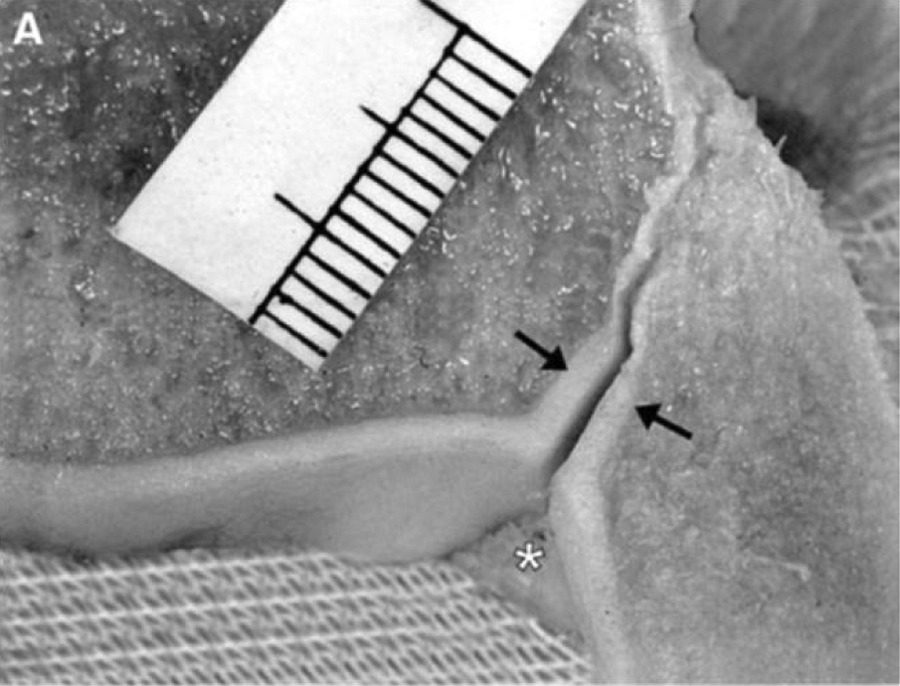

Рис. 4. Тибиофибулярная контактная зона (вид снизу, кадаверный препарат). 1 — хрящевая часть (истинный синовиальный сустав, высота 4 мм, длина 8 мм); 2 — центральная часть с V-образной синовиальной складкой. Стрелка указывает на верхнюю границу (уровень межкостной связки). Границы контактной зоны: БММС сверху, ПНБМс спереди, ЗНБМС сзади.